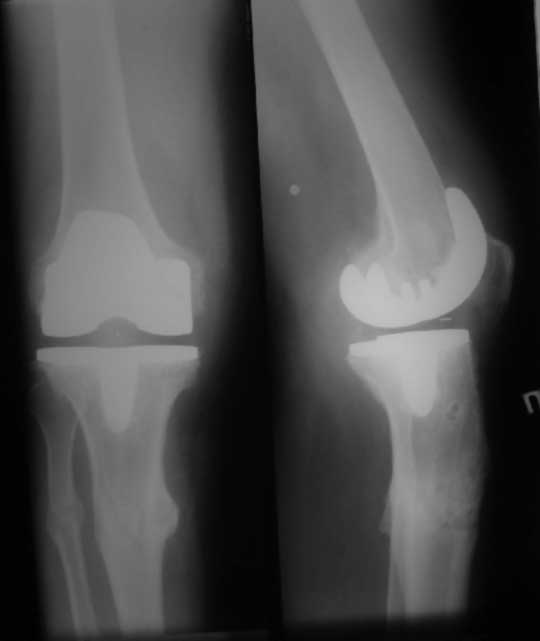

У пациента 50 лет имеется разгибательная контрактура через 8 меспосле ТКА. Уважаемые коллеги. Пациент 8 мес после операции ТКА, в анамнезе – неправильно сросшийся перелом голени, коррекция оси (снимки прилагаются. В настоящее время имеется разгибательная контрактура 10/5/0, на операционном столе было 90/0/5, на момент выписки движения 50/0/0 в надежде на дальнейшую разработку. До эндопротезирования 40/10/0. Глубокая инфекция исключена. Ротация бедренного компонента в норме (по КТ). Вопросы: насколько для такого ограничения критична некорректная установка б/б компонента (я намерял 7 град)? Причина нынешнего состояния, артрофиброз? Какие действия следует предпринять, удаление рубцов, релиз головок 4-главой мышцы? Что-либо другое, ваше мнение? С уважением, Максим Агалаков, Екатеринбург.

Рентгеновский снимок хороший, операция выполнена достойно, надколенник не смущает. Остаюсь на своем мнении, артролиз, если смущает давление надколенника при артроскопии помимо артролиза верхнего заворота, боковых каналов и переднего отдела, дополните латеральным релизом надколенника, чтоб уменьшить натяжение.

Низковат, соласен. Соориентируетесь при операции, если ограничивает движения, перенести бугристость или Z-образная тенотомия связки надколенника, артросокпический артролиз обязательно.